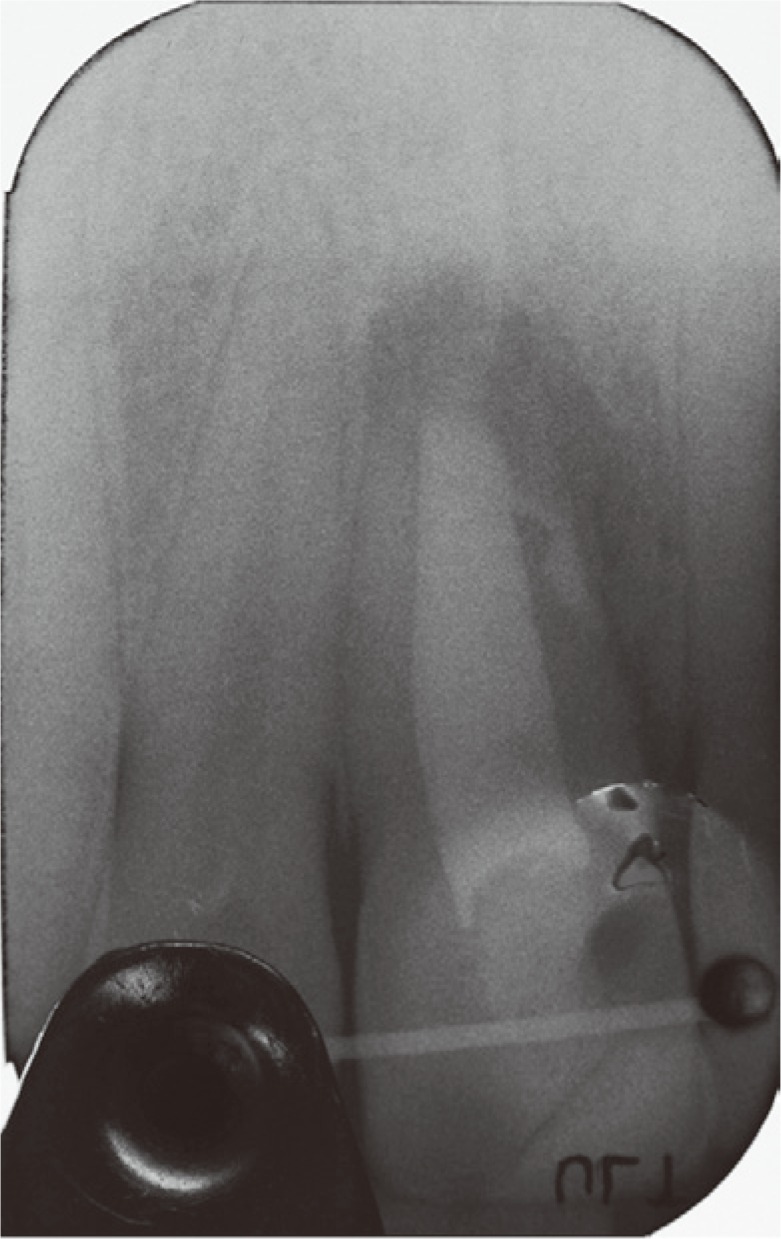

A clinical examination showed a moderate swelling on the vestibular side in the region of tooth #21, as well as the presence of a sinus tract in the same area, approximately 4 mm from the gingival margin (Figure 1). A narrow periodontal defect 7 mm in depth was present on the buccal side, as evaluated using a periodontal probe. A radiographic examination performed before surgery using both periapical radiographs and CBCT (J. Morita MFG Corp., Kyoto, Japan) revealed a root-end resection, a periapical radiolucency, and a widening of the periodontal ligament space at the mesial aspect of the root, although no hair-like fracture line radiolucency was noted in the tooth, except in the CBCT horizontal projection that showed an incomplete VRF 3 mm from the apex (Figure 2).